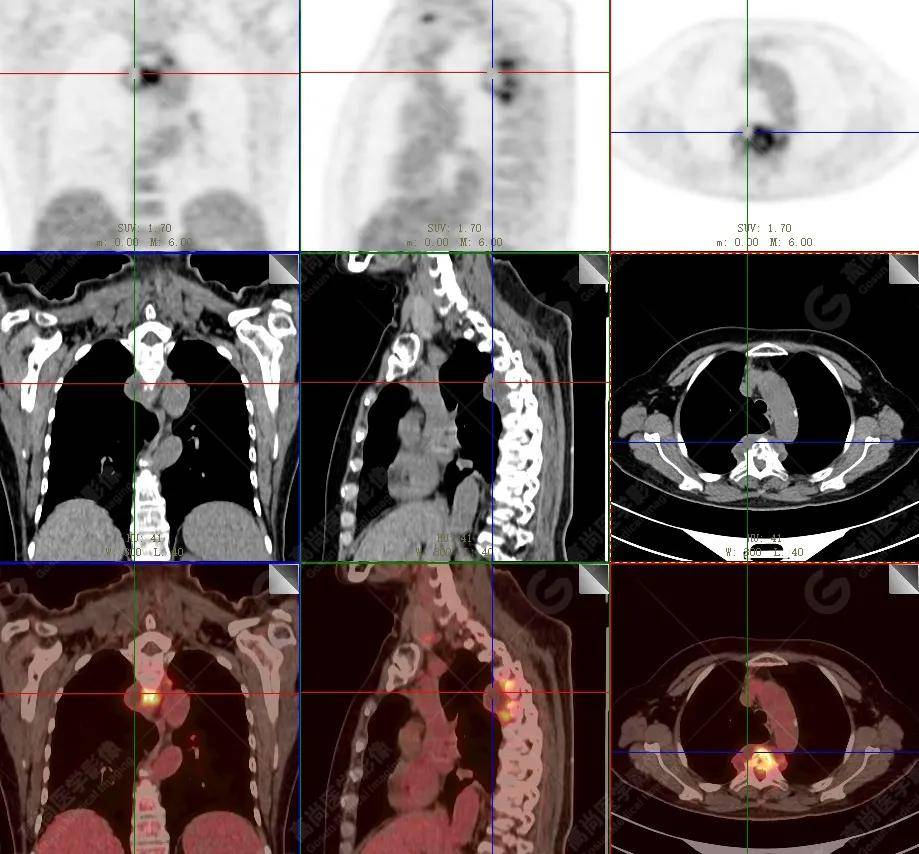

【高尚病例】18f-fdg pet/ct显像应用于骨结核